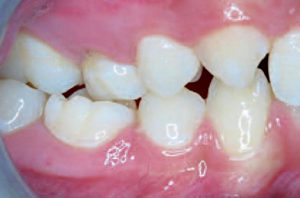

- 5a. De occlusie van een 14-jarig meisje dat een schommel tegen de 21 heeft gekregen en die na enige tijd een bruingele verkleuring vertoont.

- 5b. De occlusie van een 14-jarig meisje dat een schommel tegen de 21 heeft gekregen en die na enige tijd een bruingele verkleuring vertoont.